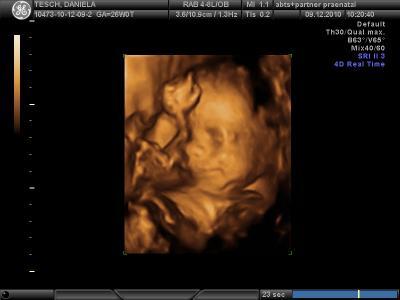

Hier endlich auch mal ein Bildchen vom meinem Wurm..

...ach ist das alles aufregend. Und grinst er nicht nieeeeeedlich... Liebe Grüße Daniela

Wow, wie süss :) und vor allem wieviel man schon erkennen kann. Ich möchte auch umbedingt eins haben :) *neidisch bin* lg Dani

Hey, das Bild sit ja der Wahnsinn. Wirklich schön und hübsch der kleine

Wow, das ist echt ein süüüüüßes Bildchen. Aber wenn ich ehrlich bin, sieht es aus als würde Dir dein Zwerg ein Vogel zeigen LG Kerstin